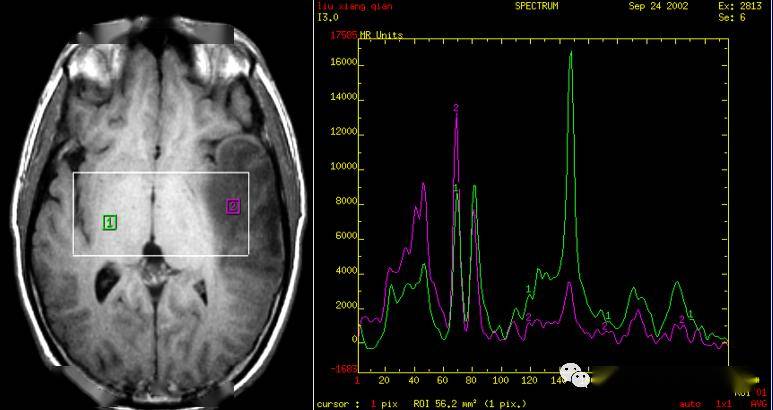

一文读懂磁共振波谱(mrs)成像_ppm_代谢_choline

图片尺寸702x460